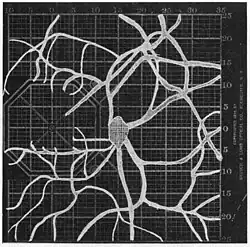

Angioscotomas were first discovered and mapped out by John Norris Evans (1891-02-28--1953-04-08)[2] in 1926, who coined the term angioscotometry to describe the painstaking charting of the scotoma of the retinal blood vessels by manual perimetry. He seated each subject in a seat in a dark setting, and tested whether they could see a tiny bright test object placed at various locations.[3] Using a 1.5 mm white disk, Evans reported intricate branch‑like scotomas that mirrored the arteries and veins emerging from the optic disc, with a full map requiring up to 2 hours to complete. He plotted this for subjects under various conditions, such as while holding breath, with glaucoma, etc. A year later, he confirmed that only short stump‑like scotomas had been noticed previously, some further data plotted with a smaller 1 mm stimuli, and under varying conditions on the subject.[4] He published a monograph on this in 1938 in which he described its use in assisting diagnosis of various conditions, such as retinal edema, glaucoma, optic neuritis, etc.[5]

1. Pressure on globe shows only stumps of large vessels. 2. Holding the breath causes similar effect; also 3. Holding the head low. 4. Pressure on opposite eye widens arteries and still more veins, 5. Pressure on the carotid produces no definite effect. 6. Looking thru red glass brings out finer vessels.

1. Pressure on globe shows only stumps of large vessels. 2. Holding the breath causes similar effect; also 3. Holding the head low. 4. Pressure on opposite eye widens arteries and still more veins, 5. Pressure on the carotid produces no definite effect. 6. Looking thru red glass brings out finer vessels. -